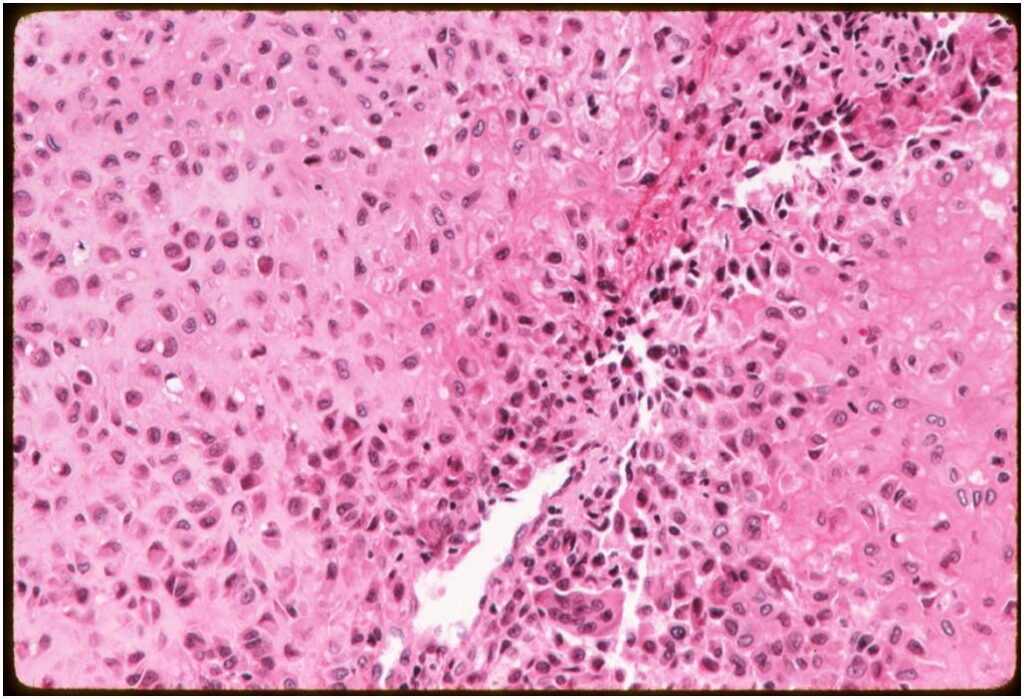

General Information Enchondroma is a benign indolent intramedullary hyaline cartilage neoplasm Accounts for 10% of all benign osseous tumors Limited growth, most lesions are less than 5 cm in maximal dimension Bones grow from a cartilaginous growth plate that...